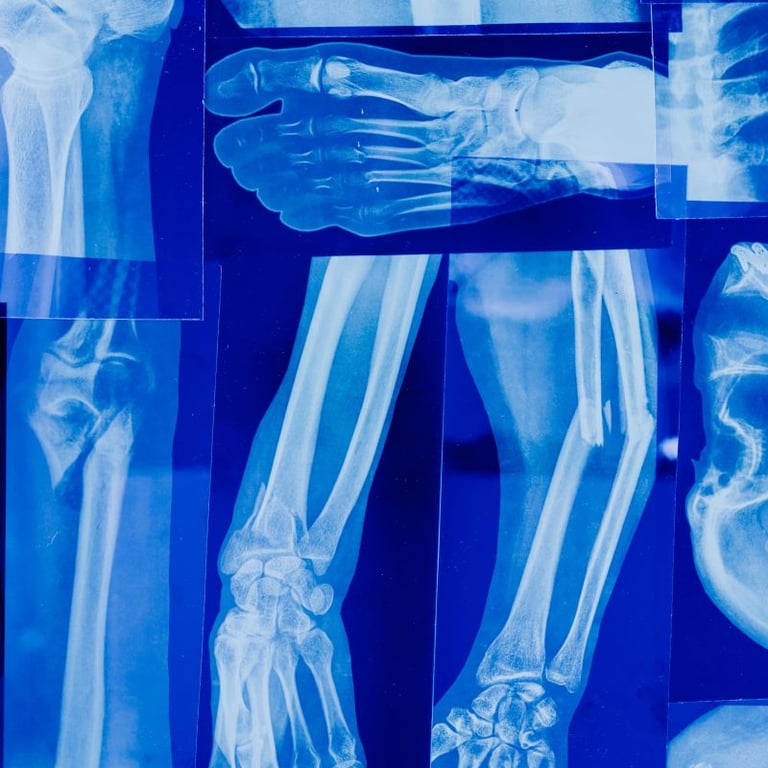

Osteoporosis is a silent threat, weakening bones over time and increasing the risk of fractures, especially for women over 65, who are disproportionately affected. But the good news is: You can take action to strengthen your bones and protect your future mobility.

The key? Strength training. When you challenge your muscles, you also stimulate your bones, encouraging them to stay strong. Think of it this way: Bones need resistance, just like muscles, to maintain their density. Exercises like squats, lunges, and resistance band workouts activate osteoblasts, the bone-building cells that keep your skeleton strong. Without this stimulation, bone breakdown (led by osteoclasts) accelerates, increasing your risk of fractures.